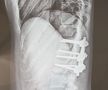

Și-a făcut arc din oase frânte! Povestea INCREDIBILĂ a Andei: „Eram studentă, un copac a căzut peste mine pe stradă” » A transformat ghinionul în vis olimpic: „Dacă eu pot, pot și ceilalți. Fără scuze!”

Foto 1/41 : Anda Arghir și tatăl ei